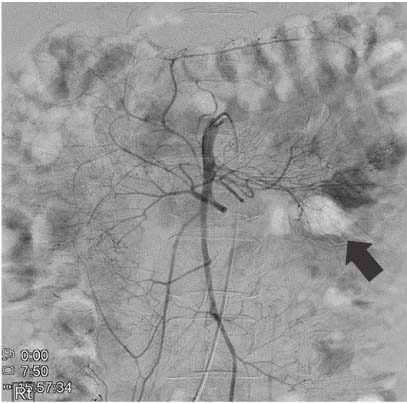

Fig. 2

Superior mesenteric artery angiography. Active extravasation is noted from the 1st jejunal branch (black arrow).

Fig. 2 Superior mesenteric artery angiography. Active extravasation is noted from the 1st jejunal branch (black arrow).